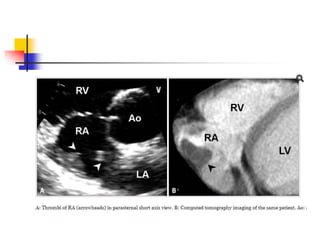

 Thrombi in the RA may mimic anatomic variants .

Clinical settings would help a diagnosis.

 Migrating free thrombi appears highly mobile snake-

like structure mimicking Chiari network.

 migrating thrombi is thicker than Chiari network, and

the end of thrombi is not fixed around the IVC orifice.

 Thrombi inthe RA may mimic anatomic variants . Clinical settings would help a diagnosis.  Migrating free thrombi appears highly mobile snake- like structure mimicking Chiari network.  migrating thrombi is thicker than Chiari network, and the end of thrombi is not fixed around the IVC orifice.